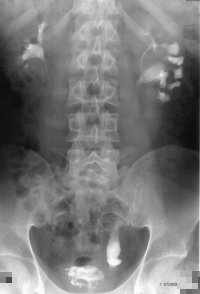

Bei dem Jugendlichen fand sich eine Doppelniere links mit hydronephrotischen Doppelnierenanteil bei VUR III.° in den unteren Anteil. Es bestand ein rezidivierender fieberhafter Harnwegsinfekt. Die Sonographie ergab eine unauffällige rechte Niere, links eine Doppelniere mit regelrechtem oberen und einem hydronephrotischen unteren Nierenanteil (Abbildung 7). Die Harnblase war unauffällig. Im Ausscheidungsurogramm fand sich eine Doppelniere links mit dilatiertem unteren Nierenanteil bei Ureter duplex (Abbildung 8a). Der Kontrastmittelabstrom aus dem unteren Nierenanteil war verzögert (Abbildung 8b). Im Zystogramm fand sich ein Vesikoureteraler Reflux (III.°) in das untere Nierenhohlraumsystem. In der Zystoskopie zeigte sich ein Golflochostium des fehleinmündenden unteren Harnleiters links. Die Nierensequenzszintigraphie ergab in der Gesamtclearence 288 ml/min (NB: > 255 ml/min) (Abbildung 8c).